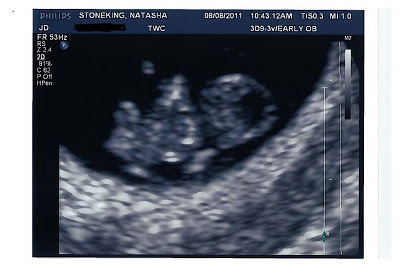

We all know the school-age rhyme of what comes next, right? For those who may not, it goes a little something like this: “The Baby in the Baby Carriage” And if you’re sitting there wondering what is going on…this picture may provide some further insight to the situation: Yes, friends, it’s true…I can finally proclaim […]

First Comes Love, Then Comes Marriage, Then Comes…